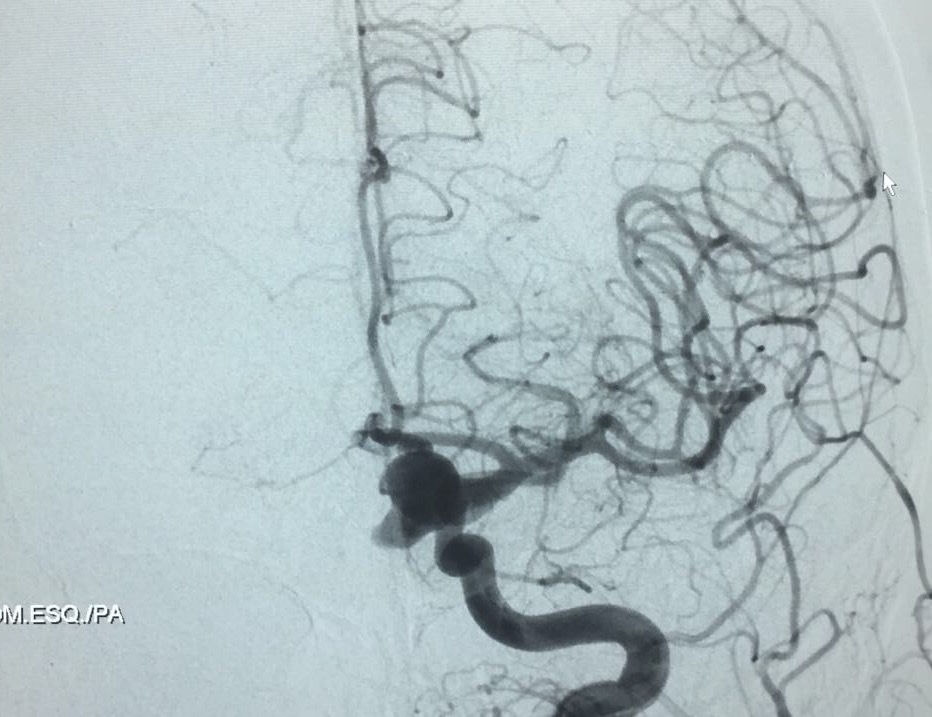

Embolização de Aneurisma segmento Oftálmico

MAP, 67 anos. Foi encontrada por sua filha no chão do banheiro de sua casa, na manhã de quinta-feira (21/09/17). Encaminhada até o setor de emergência do hospital próximo de sua casa onde foi realizado exame de tomografia de crânio evidenciando sangramento ativo (Hemorragia subaracnoidea) de provável origem aneurismática. As imagens de tomografia de crânio não foram liberadas em sistema para divulgação, mas se tratava de sangramento cerebral com classificação de sangramento subaracnóide Fisher IV ( inundação ventricular) e sem sinais de hidrocefalia.  Segundo informações de prontuário a mesma se encontrava em bom estado neurológico no momento em que foi atendida pela equipe médica, classificando como escala de Hunt-Hess II ( Cefaléia moderada a severa e rigidez de nuca), não apresentando sinais de acometimento de pares cranianos.

Paciente foi então encaminhada ao setor de hemodinâmica sendo realizado Angiografia cerebral Digital e evidenciado aneurisma de segmento oftálmico da artéria carótida interna esquerda. Realizado embolização do aneurisma com microespirais, sem intercorrências. A paciente permanece em bom estado geral e neurológico recuperando em pós operatório imediato.